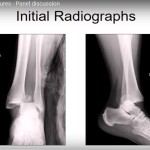

Case discussions on Distal Tibia and ankle fractures

Panel Discussion on Post traumatic deformity and Nonunion